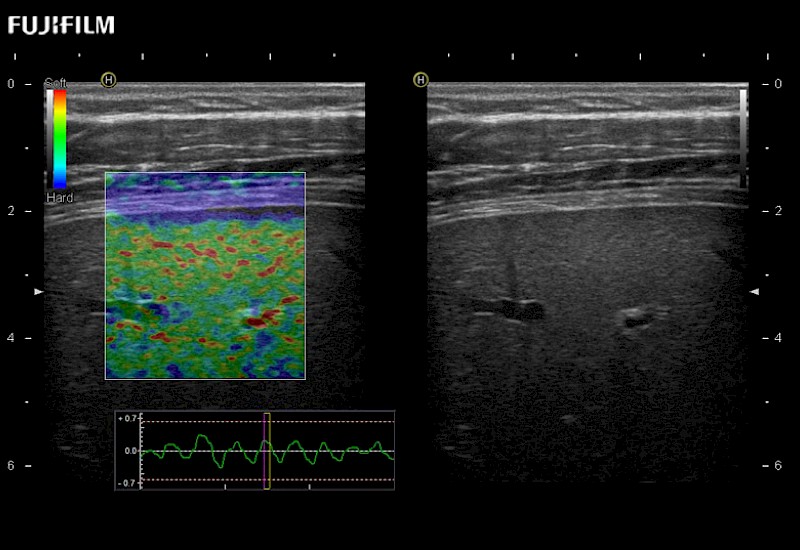

The ARIETTA 750 incorporates all of the proven technologies and functions that medical professionals have come to expect from Fujifilm Healthcare.

ARIETTA 750 is the definitive diagnostic ultrasound solution for any clinical setting - Private Office, Imaging Center, or Hospital. The ARIETTA platform provides the ultimate in clinical performance with its state-of-the-art features and large user-friendly display.

The ARIETTA 650 DI combines trusted Fujifilm Healthcare technologies and features tailored for surgical oncology.

Designed to meet the demands of surgeons, the ARIETTA 650 DI offers precise guidance. Its advanced capabilities and large, intuitive display offer accurate and efficient care in operating rooms and specialized surgical settings.

Guidance is the fundamental purpose for all of our surgical ultrasound technology. Fujifilm Healthcare is committed to designing tools that help neurosurgeons navigate inside the human body and provide the necessary information to immediately make critical surgical decisions.

With the ARIETTA Precision the next level of surgical ultrasound is here.